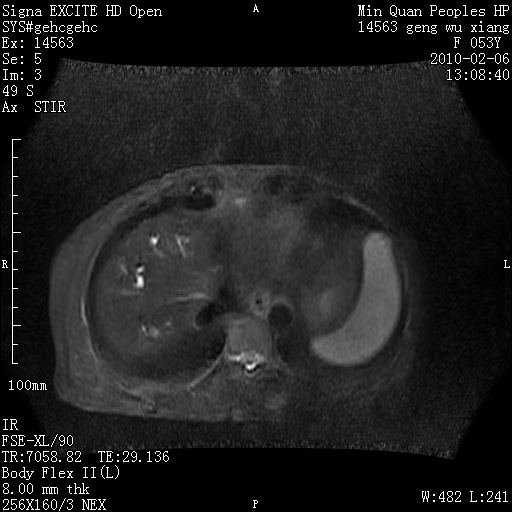

标题: MRI2762:胆道梗阻原因?

f,53y,全身黄染多日。

高位胆道梗阻 胆管癌可能性大

支持 高位胆道梗阻 胆管癌可能性大。